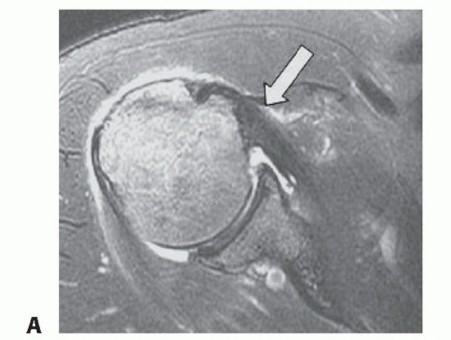

DEFINITION Symptomatic recurrent posterior instability represents up to 12% of all cases of shoulder instabil…